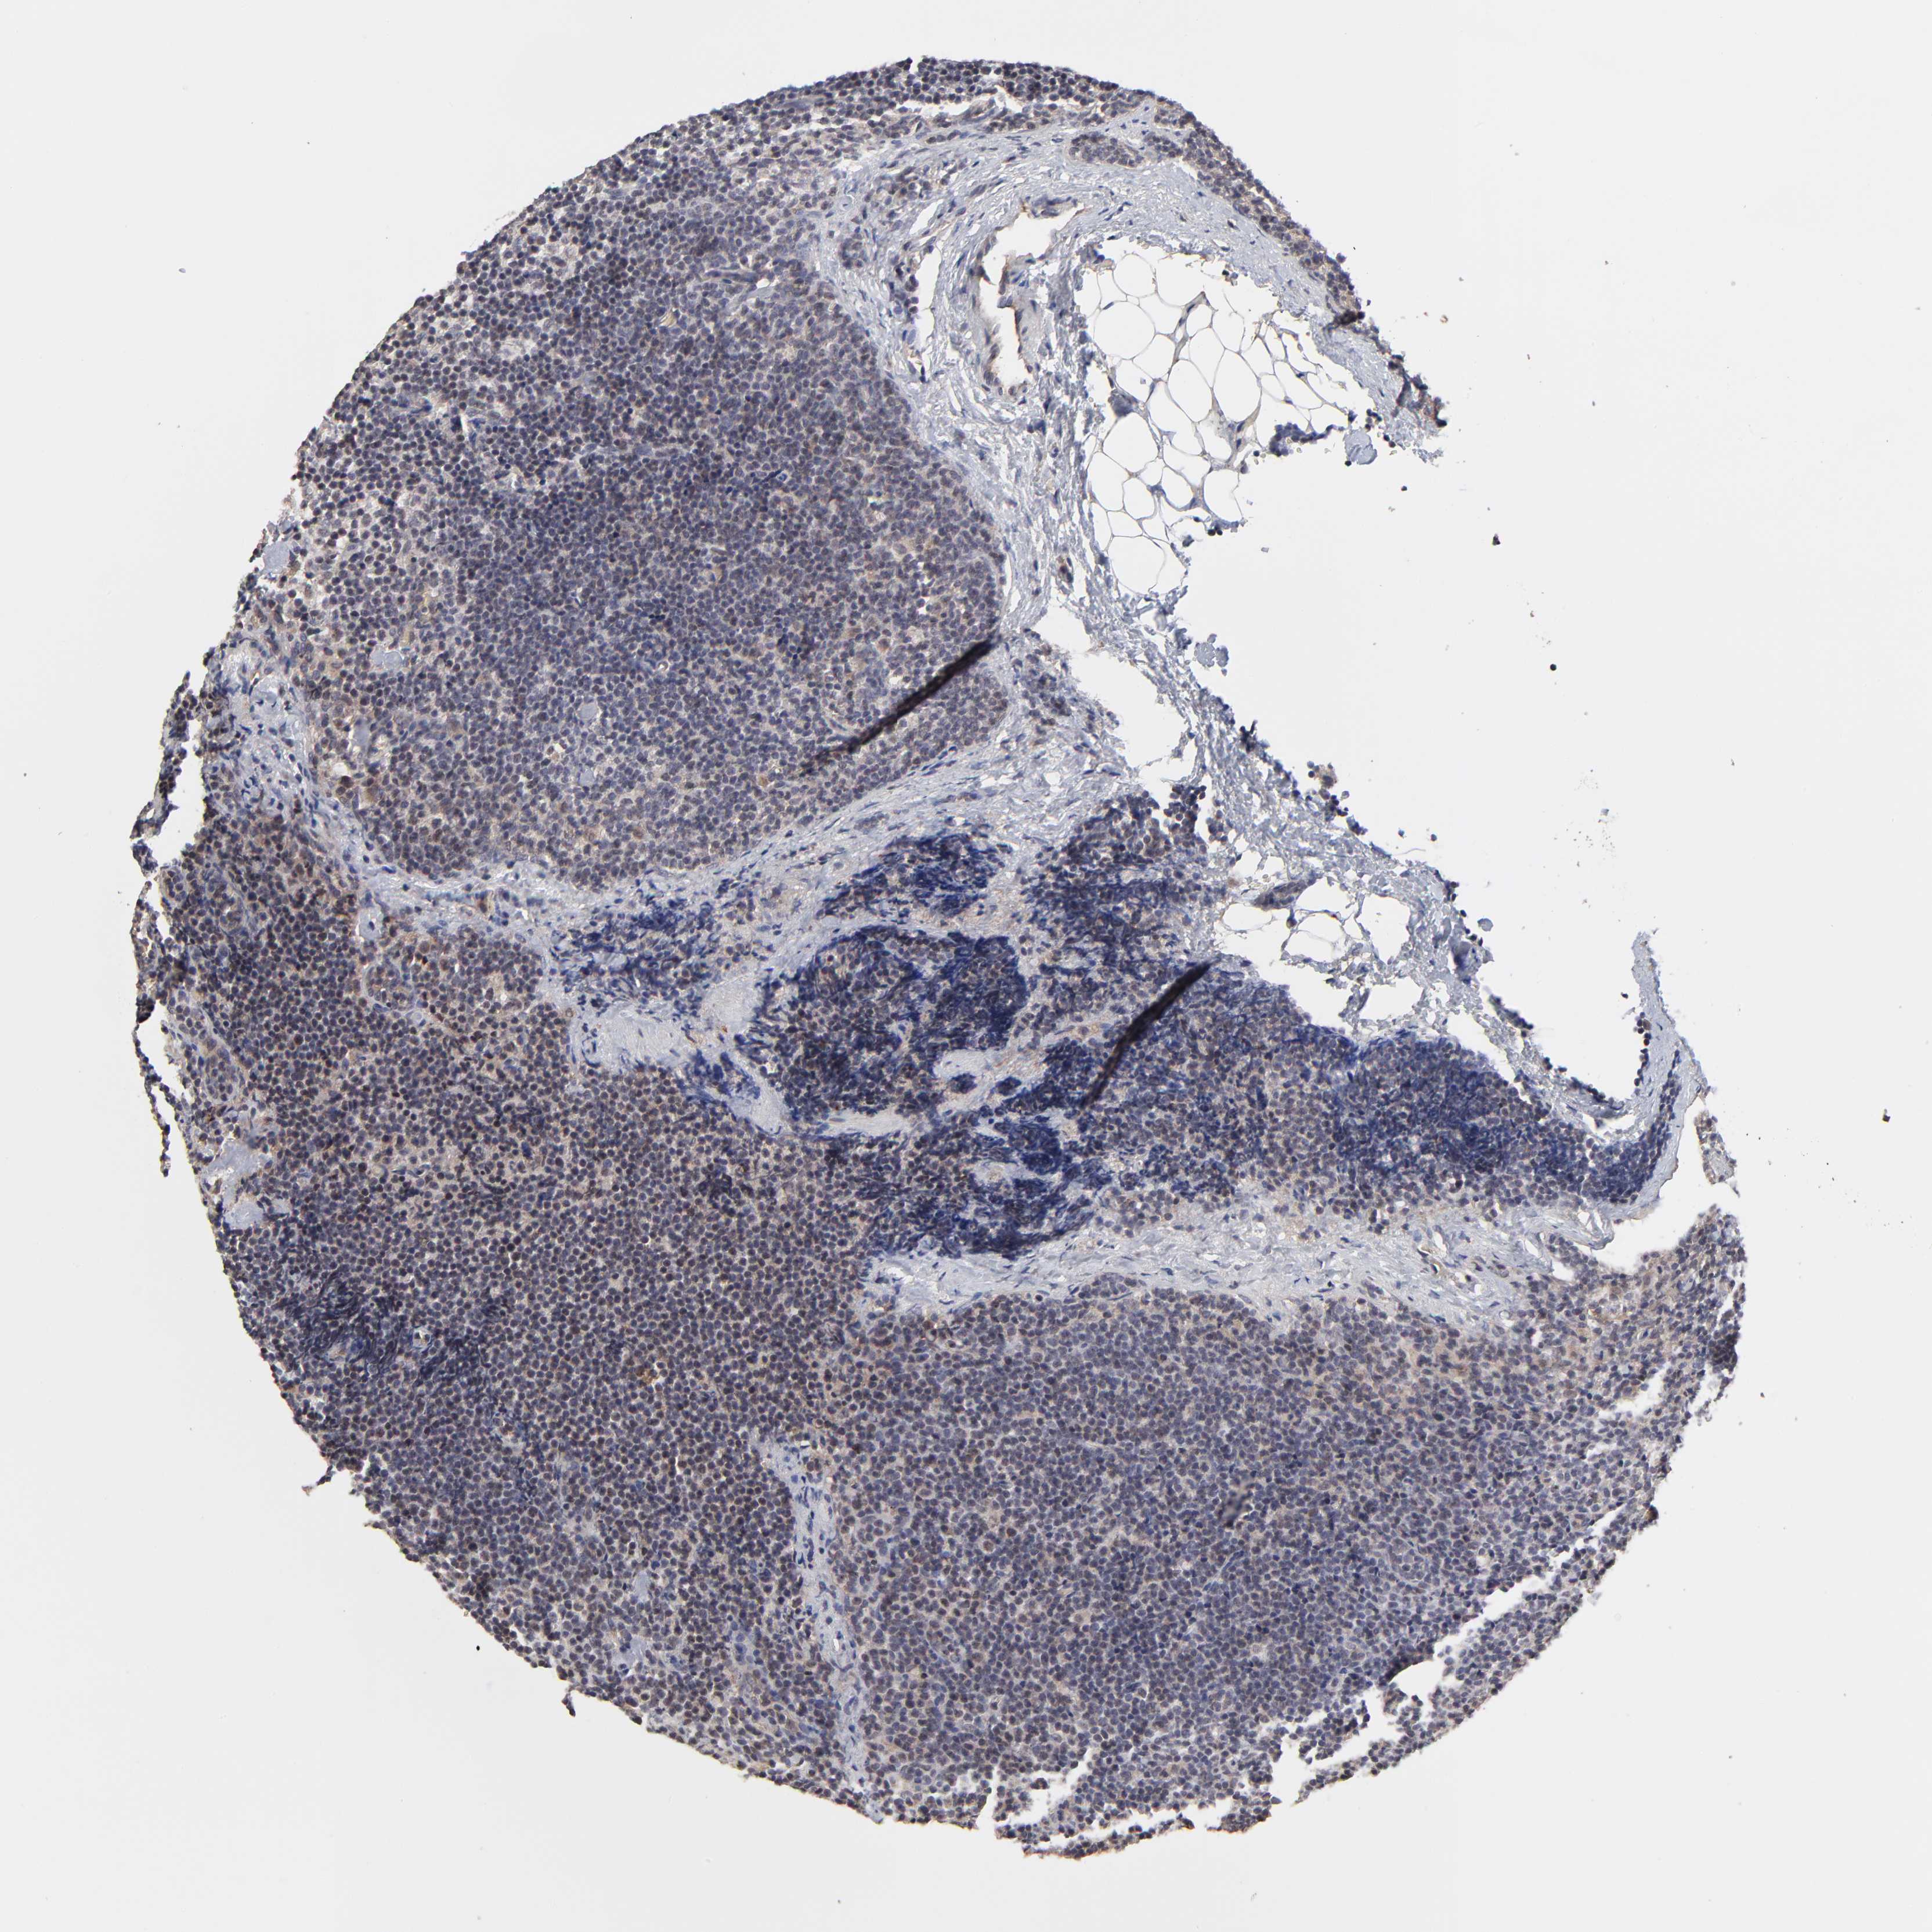

LYMPHOMA - Protein expressioni

A mouse-over function shows sample information and annotation data. Click on an image to view it in a full screen mode. Samples can be filtered based on level of antibody staining by selecting one or several of the following categories: high, medium, low and not detected. The assay and annotation is described here.

Antibody staining in the annotated cell types in the current human tissue is reported as not detected, low, medium, or high, based on conventional immunohistochemistry profiling in selected tissues. This score is based on the combination of the staining intensity and fraction of stained cells.

Each image is clickable and will lead to virtual microscopy that enables deeper exploration of all samples and also displays staining intensity scores, fraction scores and subcellular localization as well as patient and tissue information for each sample.

Antibody HPA002861

Staining

High

Medium

Low

Not detected

Intensity

Strong

Moderate

Weak

Negative

Quantity

>75%

75%-25%

<25%

None

Location

Nuclear

Cytoplasmic/membranous

Cytoplasmic/membranous,nuclear

Malignant lymphoma, non-Hodgkin's type, High grade

Hodgkin's disease, NOS

Malignant lymphoma, non-Hodgkin's type, Low grade